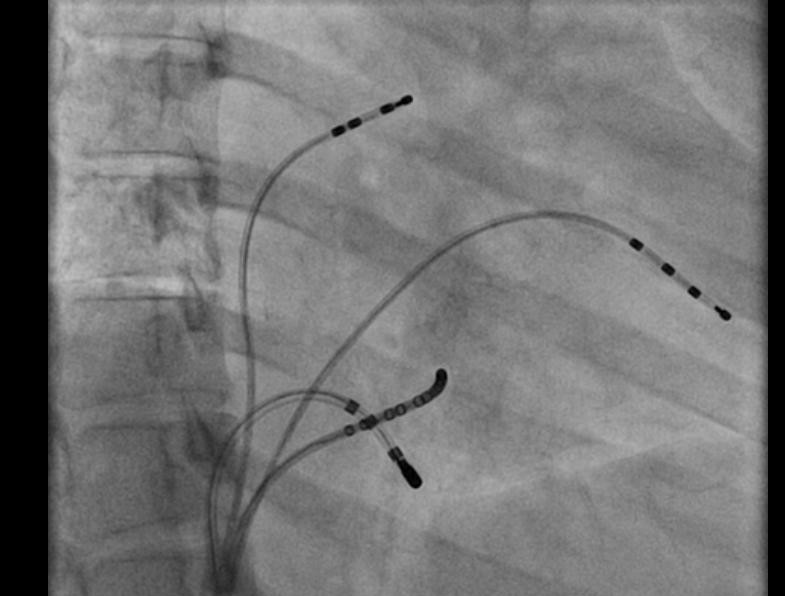

RF ablation

ablation.jpg